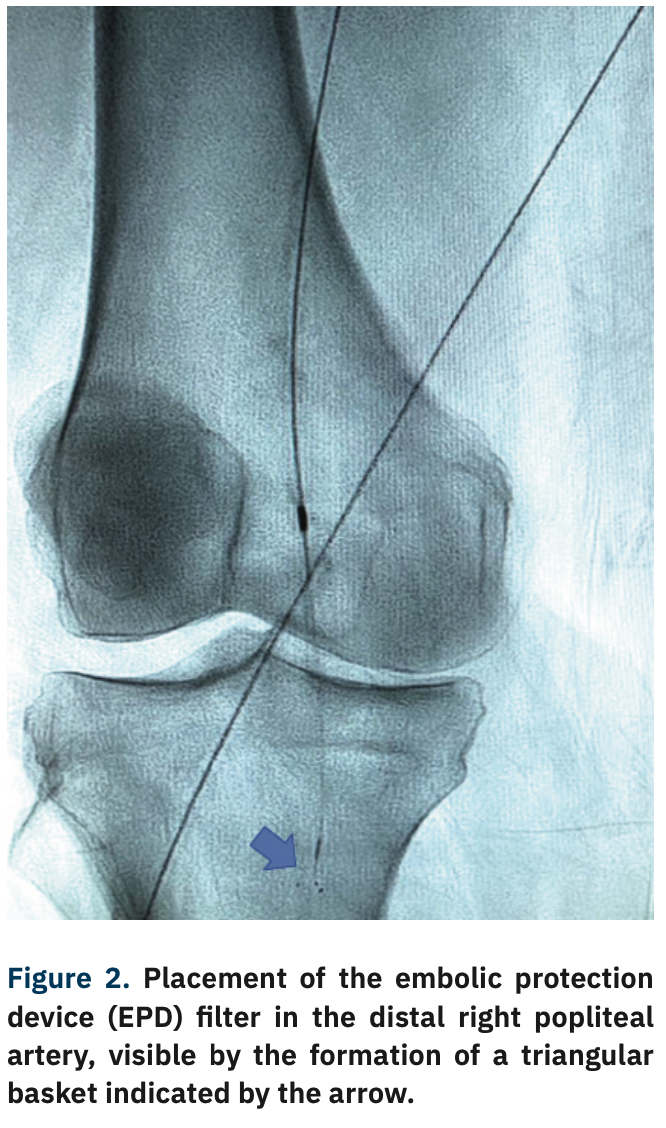

Contralateral retrograde access of the left femoral artery was obtained, and a 6 French (Fr) 45 cm sheath was advanced to the level of the right common femoral artery (CFA). A Mongo wire (Asahi Intecc) was inserted to cross the distal SFA and popliteal lesions. An embolic protection device (EPD) filter was placed in the distal popliteal artery (Figure 2). Orbital atherectomy was performed with a 1.5 solid crown Diamondback (CSI), followed by a 5 mm x 250 mm drug-coated balloon at the lesioned sites (Figure 3).